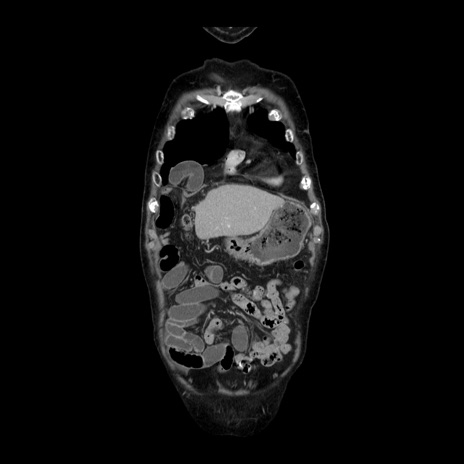

症例21(冠状断像)

【症例】70歳代男性

【主訴】腹痛

【現病歴】肝硬変・肝細胞癌にてかかりつけの方。約9時間前に食後より腹痛出現。症状が徐々に増悪し、嘔吐出現したため来院。

【既往歴】肝硬変、肝細胞癌(RFA、TACE後)

【身体所見】意識清明、表情苦悶様、BT 36℃、BP 129/78mmHg、P 88bpm、SpO2 97%(RA)、右上腹部から心窩部にかけて圧痛あり、反跳痛なし、筋性防御あり。

【データ】WBC 5800、CRP 0.16